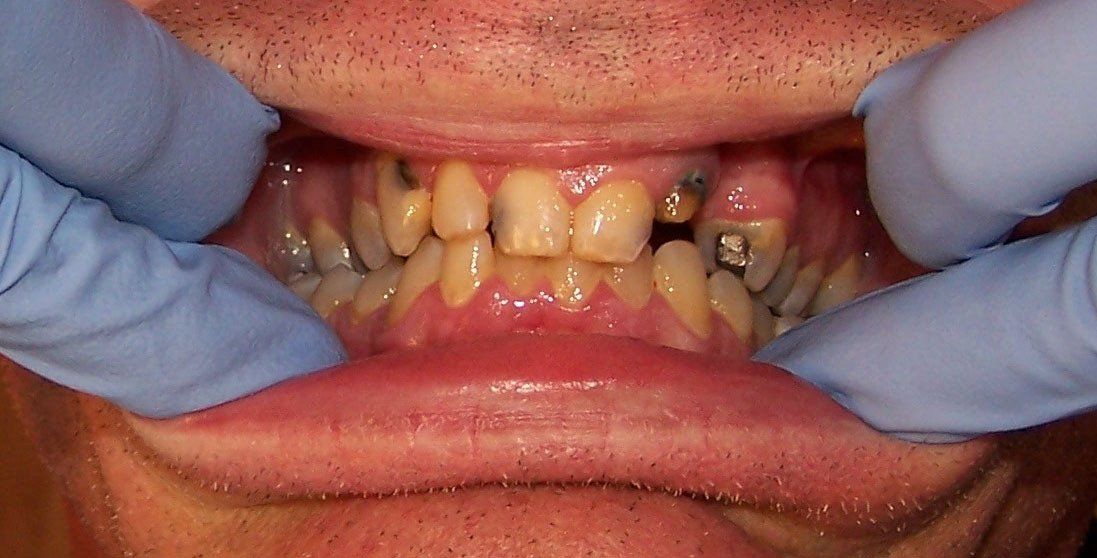

Ally Before

Holly Before

Johnson Before

Karen Before

Nancy Before

Ralph Before

Steve Before